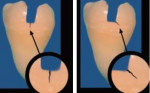

In general, there are two basic varieties of dentinal fractures: oblique and vertical. The most commonly seen fractures in dentin, which often occur under existing amalgam restorations, are the oblique fractures. These fractures run in the floor of the preparation, undermining the cusps; they run in a more horizontal direction, and they are often the precursors to a fractured cusp. When they become symptomatic, many patients will complain of a sharp and intense, but generally short-term, sensation while chewing foods, particularly when they apply lateral pressure to the cusp or cusps that are involved. In the literature, Fennis et al found that oblique complete fractures are more common on molars than premolars (79% to 21%) and occur on the maxillary buccal cusps (66% to 34%) and the mandibular lingual cusps (75% to 25%).38 Vertical fractures run mesial to distal on the tooth and may be the precursors to a split tooth. These more dangerous, vertically oriented cracks may result in devastating fractures, with pulpal and/or periodontal breakdown. The vertical fractures may progress into a split tooth that is completely fractured and unrestorable (Figure 2A and Figure 2B).

According to Clark, the more ominous type of fracture is vertical in direction. Vertical fractures run in a mesial to distal direction and are more commonly associated with thermal sensitivity in addition to chewing sensitivity. These fractures are more commonly associated with teeth that either have or will develop irreversible pulpitis and should be treated expeditiously with full-coverage restorations. On these teeth, the author will often cement the final restoration provisionally for a period of 2 to 3 months to evaluate whether the tooth requires endodontics when symptoms are not present initially or are mild in nature. Vertical fractures can be found in teeth that are not symptomatic and still vital. They are a precursor to a complete vertical fracture and should be treated quickly and comprehensively to avoid devastating fractures that would result in the need for extraction.